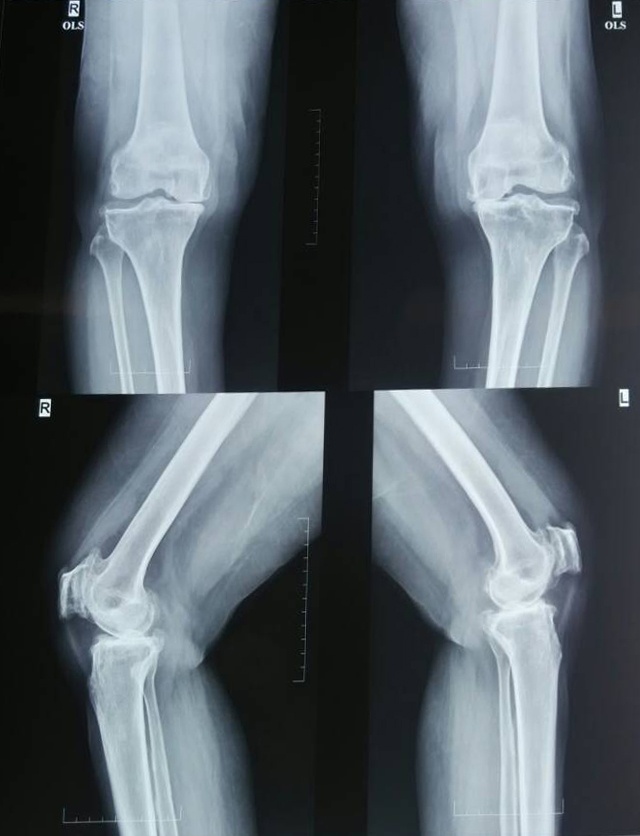

S-adenosyl methionine-Before treatment

S-adenosyl methionine-After treatment

X-Ray 3: The anteroposteiror and lateral view of the knee joint before and after treatment with S-adenosyl methionine

X-ray 3 shows the knee joint surface before and after treatment of S-adenosyl methionine. Pre-treatment X-ray shows mild narrowing of medial intercondylar joint space with subchondral sclerosis and minimal osteophytes. Femoropatellar joint joint space appears narrowed with retropatellar osteophytes. Post-treatment X-ray shows no significant radiological changes observed in the affected knee joint even after 12 w of treatment with S-adenosyl methionine.